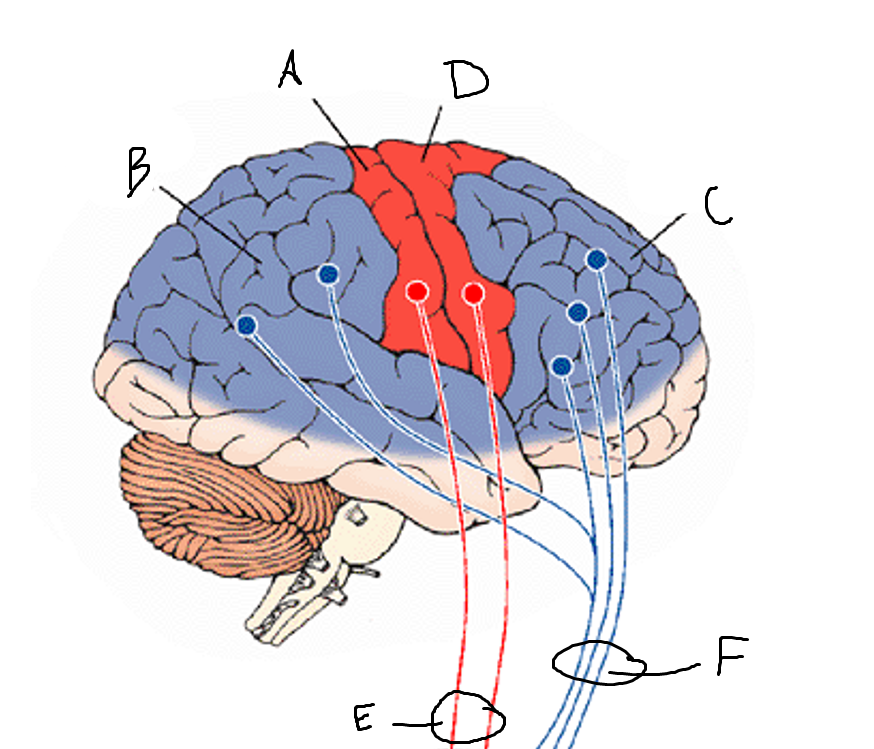

basal ganglia

A

somatosensory cortex

B

parietal association cortex

C

frontal and prefrontal cortices

D

primary motor cortex

E (where are the projections?)

putamen

F (where are the projections?)

caudate